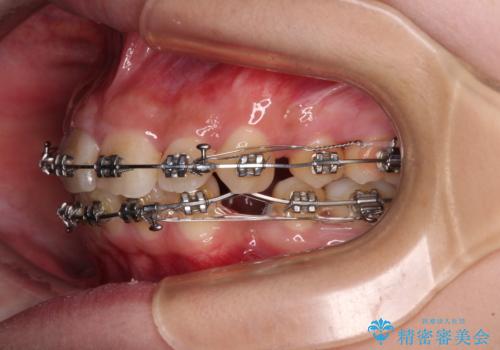

下顎前歯が隠れて突出した口元 ワイヤー装置での抜歯矯正

- 矯正装置

- メタルブラケット

- 治療計画

- 前歯のデコボコと口元の突出感を気にして来院された患者様です。

下顎骨の左右差や、上顎骨の前方位などが認められたため、上下左右の第1小臼歯4本を抜歯し、ワイヤー装置にて矯正治療を行うこととしました。

骨格的な左右差がありましたが、何とか当初予定していた期間で、左右対称の咬み合わせに仕上げることができました。